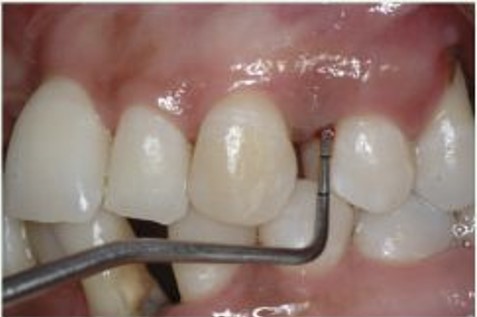

Profundidade de Sondagem aumentada

Exame Radiográfico

O exame Radiográfico é muito importante, deve ser observado o volume e a posição da crista óssea para que se tenha uma melhor condição de previsibilidades, viabilidade e escolha da técnica a ser utilizada. (RX Periapical e Interproximal)